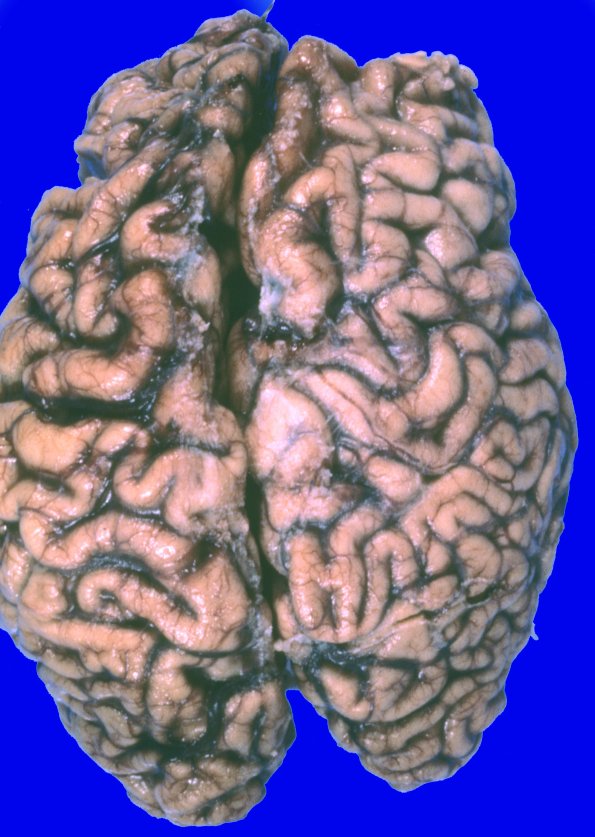

External examination of the brain showed marked diffuse cortical atrophy.